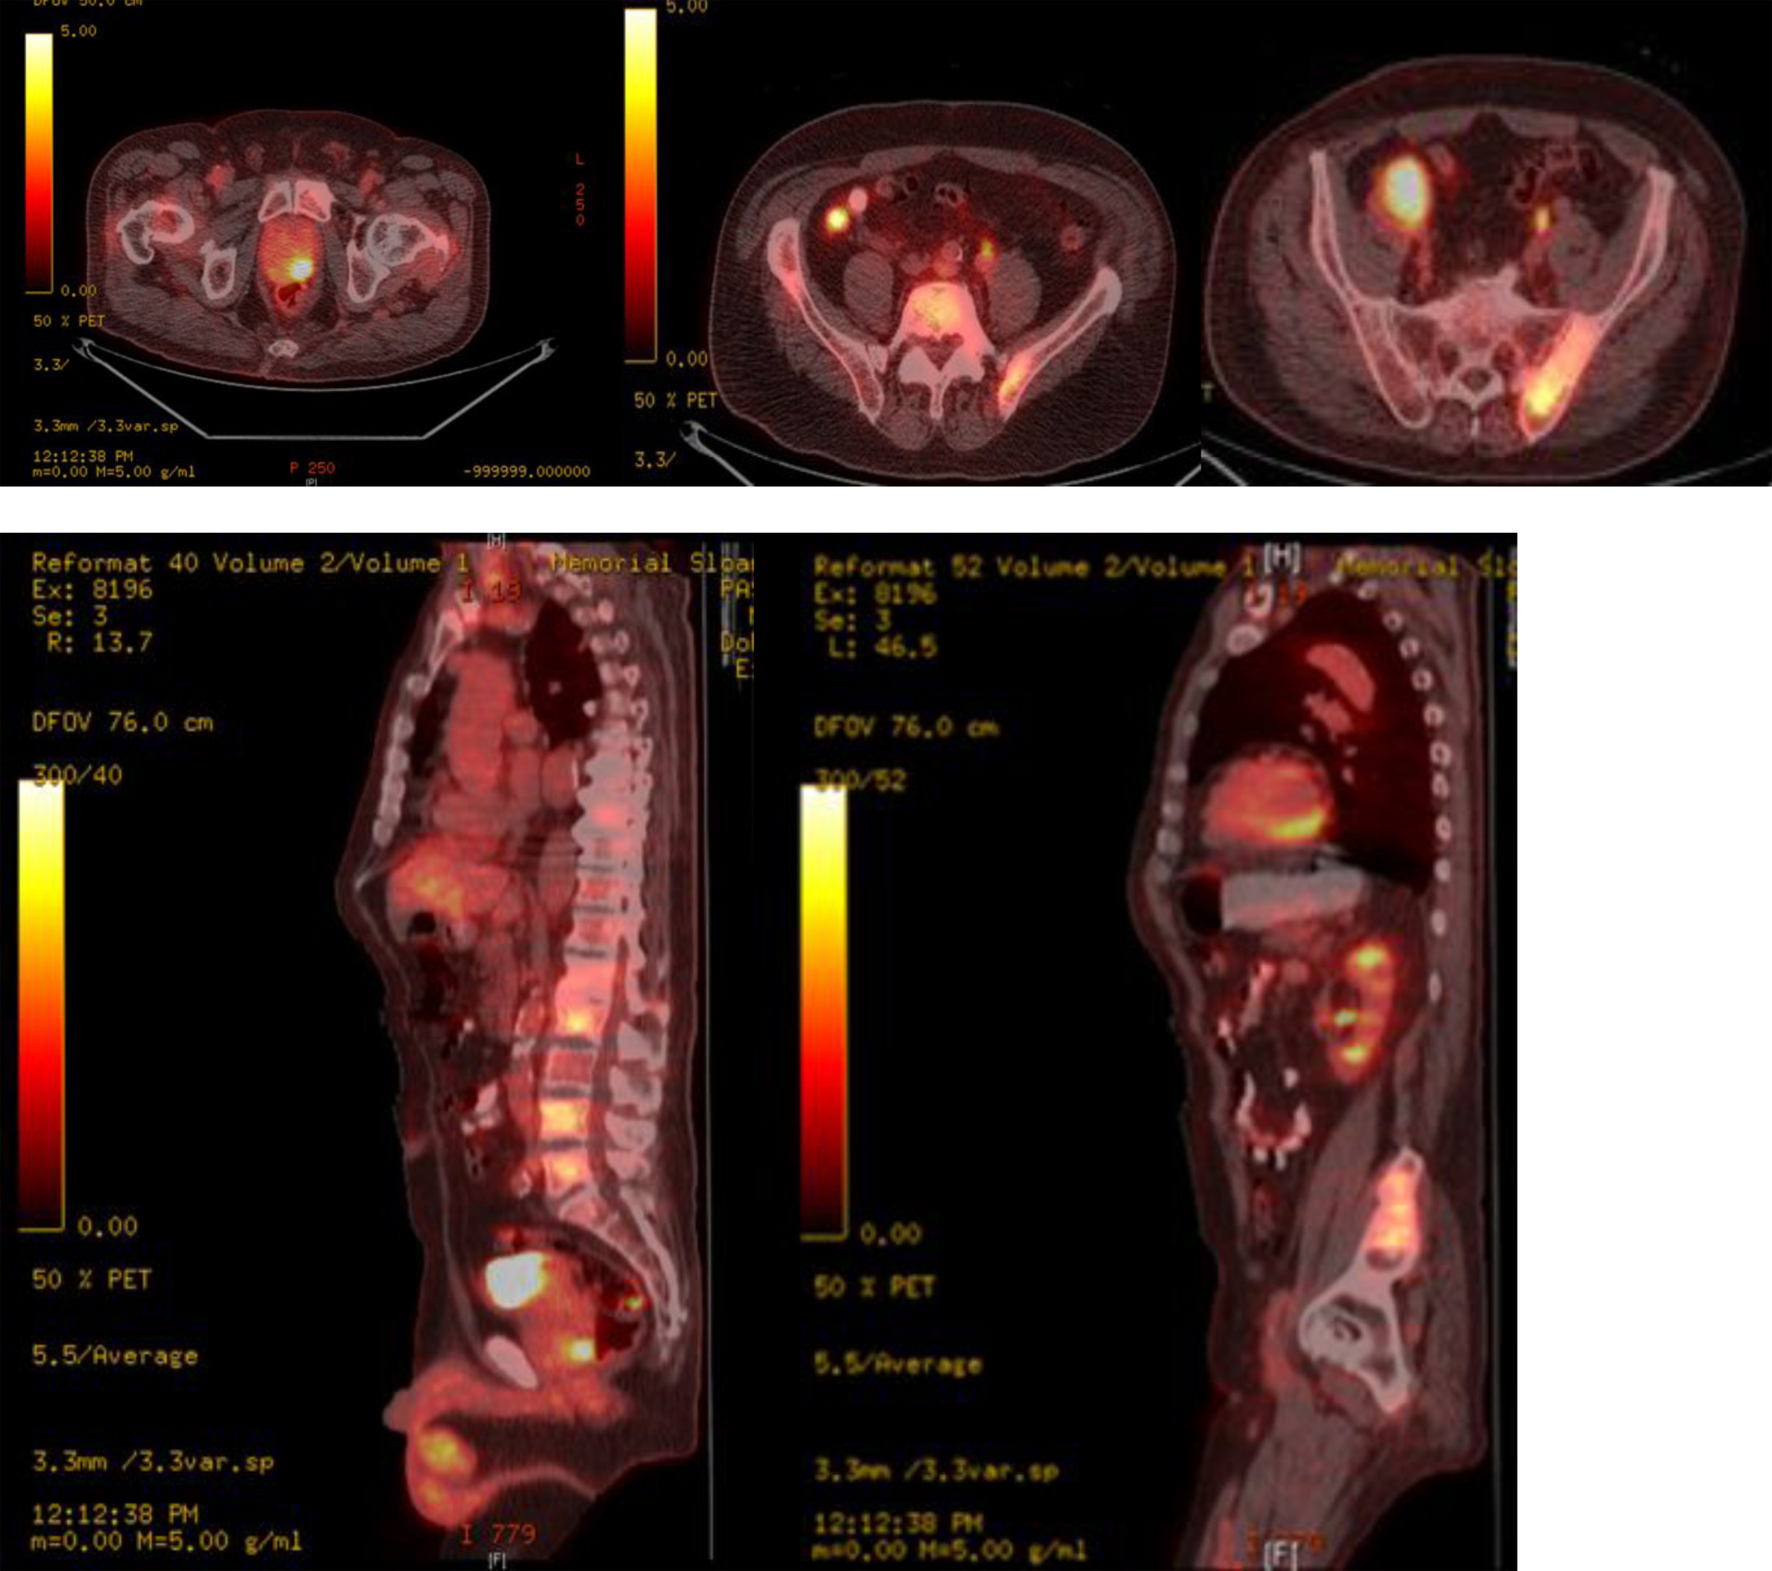

A thorough systemic evaluation was performed to look for a primary source of malignancy. Laboratory work-up revealed a normal complete blood count and comprehensive metabolic panel except for an elevated alkaline phosphatase level of 317 units/L (normal range: 49 - 129 units/L). Whole body PET-CT showed: an FDG avid mass in the right posterior orbit extending into the ethmoidal cells (SUV 4.2), FDG avid focus in the left posterior aspect of the prostate gland suspicious of a malignancy (SUV 8.9), bilateral FDG avid enlarged iliac nodes (SUV 6.1 - 6.3) and multiple FDG avid sclerotic bony lesions, suspicious of metastasis (Fig. 2).

![]() Click for large image | Figure 2. Whole body PET-CT showing FDG avid uptake in posterior lobe of prostate, axial spine, iliac bones and bilateral iliac lymph nodes. |